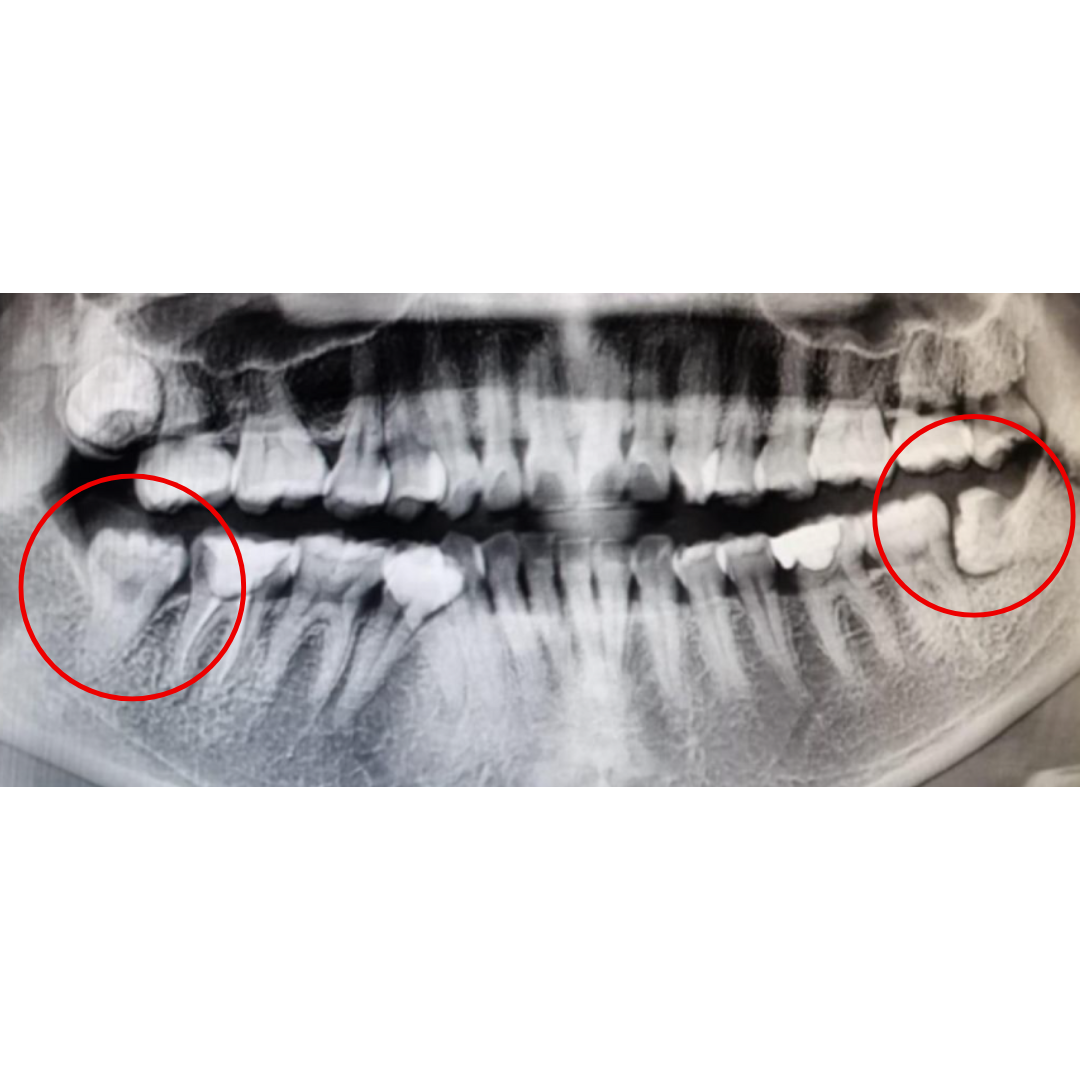

Impacted Wisdom Teeth

Wisdom teeth that grow sideways, are stuck (impacted), or push against other teeth can cause pain, swelling, and infection. Minor Oral Surgery (MOS) safely removes them to prevent complications.

Before & After

📸 Before: Swelling, impacted tooth, or severe infection

📸 After: Healed gum with restored comfort & function

Patients often feel a big relief after MOS because the source of pain or infection is removed.